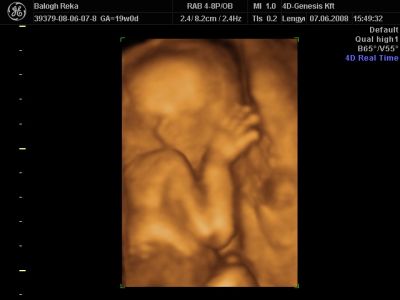

Huhh, hát annyira jó élmény volt, most tök boldog vagyok! Nagyon örülök, hogy mégis elmentem mégegyszer, mert sokat vacilláltam ám. A 4D Genesis egyszerűen szuper, mindenkinek nagyon nagyon tudom ajánlani, ezen belül is engem a Lengyel Györgyné Márti fogadott. Szuper ez a nő, akkora átéléssel és profizmussal csinálta az egész vizsgálatot! Mindent részletesen megnézett, megmutatott, elmagyarázott, nem sajnálta az időt. A felvétel gyönyörű lett, az egész baby nagyon szépen látszik, végig fent volt és mocorgott, hihetetlen aranyos volt, és nagyon szép!

Bemutatott párszor, ezek mind meg is vannak örökítve!

Na és a lényeg...jöjjenek a sztárfotók! Bocsi előre, 8 lesz és kicsit nagyok, de nem tudtam választani, azokat a bemutatásokat mind muszáj volt felraknom, tök vicces!